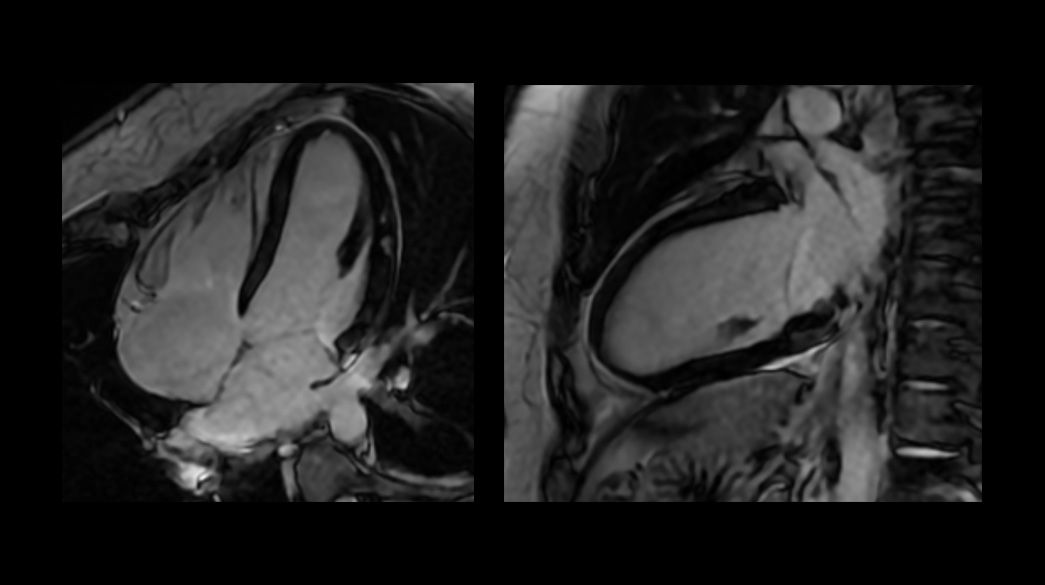

FIESTA Cine

Can be used as a gated or non-gated sequence to assess anatomy and function, with excellent tissue contrast between blood pool, myocardium and valves